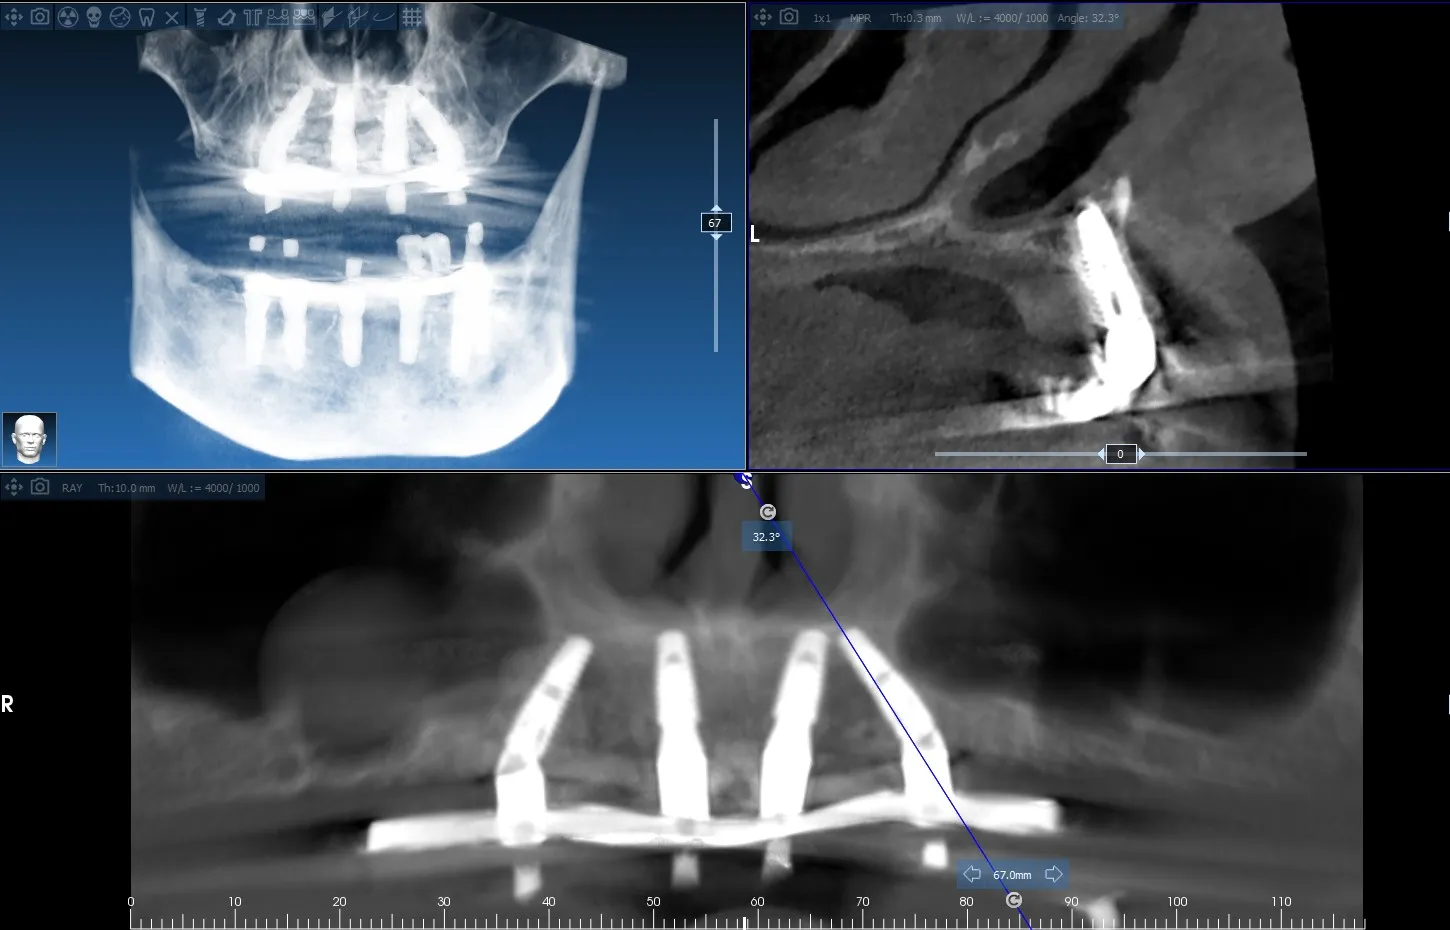

Dual Arch Rehabilitation — All-on-4 & All-on-6

Complete upper and lower jaw rehabilitation. All-on-4 concept for maxilla and All-on-6 for mandible with custom surgical guides.